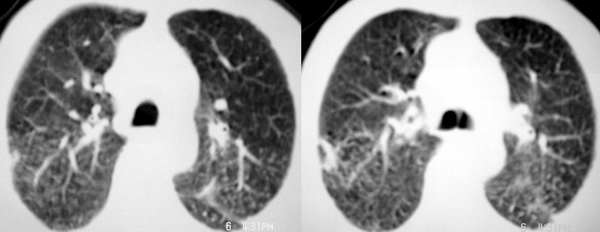

以下是引用sdqzwyx在2005-11-7 19:59:00的发言:[br]双肺弥漫大小不等的粟粒状结节影;肺纹理走行失去自然,粗细不均,边缘不规则,小叶间隔增厚;左上肺示不规则形致密影,从斑块边缘向周围伸出长短不一的致密索条影,临近的血管、支气管和叶间胸膜等结构受牵拉移位;左下肺示不规则团块状影,其内示空洞,洞内壁尚光整,左侧胸腔积液。右肺下叶背段亦示部分病灶融合。双肺可见局限性肺气肿。[br]诊断:结合病史符合三期矽肺表现(少数矽肺纤维斑块内可以形成空洞,一般认为是斑块中央感染引起坏死所致)但尘肺病人易合并肺结核,诊断可为三期+tb。所以此病人应进一步检查是否合并结核。